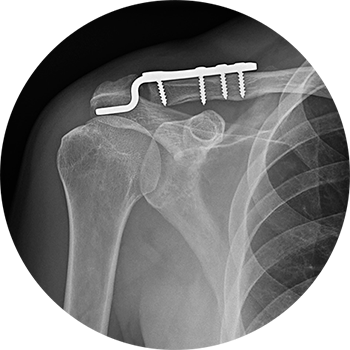

Das AC-Gelenk verbindet das äußere Ende des Schlüsselbeins (Clavicula) mit dem Schulterdach (Acromion) und ist ein integraler Bestandteil des Schultergelenkkomplexes. Es ermöglicht nur geringe Rotationsbewegungen, vor allem bei Armbewegungen über Kopf. Aufgrund seiner starken Bandführung ist das Gelenk kaum aktiv trainierbar.

Beschwerden im AC-Gelenk entstehen in der Regel durch:

Direkte Gewalteinwirkung, etwa bei Stürzen im Sport – was zu einer sogenannten ACG-Sprengung führen kann

Verschleißbedingte Veränderungen (Arthrose), insbesondere im mittleren und höheren Lebensalter

Eine akute Verletzung des Schultereckgelenks – insbesondere bei Bandverletzungen oder -rissen – äußert sich durch plötzliche, starke Schmerzen und eine sichtbare Hochstellung des Schlüsselbeins. Bewegungen im Schultergelenk sind oft nur unter Schmerzen möglich.

Im Verlauf kann es auch bei konservativ versorgten oder operierten Fällen zu späteren Arthrosebeschwerden kommen. Diese werden meist als dumpf, tiefsitzend empfunden und können in den Nacken oder die Halsregion ausstrahlen.

Die Diagnose wird in der akuten Phase häufig schon durch das klinische Erscheinungsbild und die körperliche Untersuchung gestellt. Eine deutlich hervortretende Schlüsselbeinspitze, verbunden mit lokalem Druckschmerz, gilt als typisches Zeichen. Bei chronischen Veränderungen äußern sich die Beschwerden meist durch belastungsabhängige Schmerzen, insbesondere bei Überkopfbewegungen oder bei längerem Liegen auf der betroffenen Seite.

In bestimmten Fällen kann ein diagnostischer Infiltrationstest Klarheit bringen: Hierbei wird das Gelenk gezielt betäubt, um festzustellen, ob die Beschwerden tatsächlich vom AC-Gelenk ausgehen.

Die Behandlung richtet sich nach dem Ausmaß der Bandverletzung. Leichtere Formen (z. B. Grad I–II) werden meist konservativ behandelt – mit Ruhigstellung, Schmerztherapie und späterer Physiotherapie.

Ab einem höhergradigen Bänderriss (Grad III oder höher) wird häufig eine operative Stabilisierung empfohlen. Hierbei stehen verschiedene Verfahren zur Verfügung (z. B. mit Implantaten wie Hakenplatten oder Fadensystemen), die alle vergleichbare Erfolgsraten zeigen. Wichtig ist, dass die Operation zeitnah erfolgt, um optimale Ergebnisse zu erzielen.

Besteht eine länger andauernde Instabilität, kann zu einem späteren Zeitpunkt eine aufwendigere Stabilisierungsoperation durchgeführt werden.

Bei ausgeprägter Arthrose im AC-Gelenk, die auf konservative Therapie nicht anspricht, ist eine operative Entfernung der betroffenen Gelenkanteile (Resektion) möglich. Dieser Eingriff kann sowohl offen als auch minimalinvasiv erfolgen. Ziel ist die Druckentlastung der Gelenkfläche, um Schmerzen zu reduzieren.

Nach einer operativen Stabilisierung wird der betroffene Arm für sechs bis acht Wochen ruhiggestellt, meist mit einer Armschlinge. Die anschließende Bewegungstherapie erfolgt stufenweise und unter Schonung, um das rekonstruierte Bandgewebe nicht zu überlasten. Zusätzlich helfen entzündungshemmende Medikamente und lokale Kältetherapie, um Schmerzen und Schwellungen zu kontrollieren.

Wird lediglich ein arthrotischer Gelenkanteil entfernt, ist keine Ruhigstellung notwendig. Die Schulter kann in diesem Fall frühzeitig aktiv bewegt werden – abhängig vom Schmerzempfinden. Die volle Belastbarkeit ist meist erst nach mehreren Monaten gegeben. Insgesamt kann die Erholungsphase – je nach Eingriff und Ausgangsbefund – drei bis sechs Monate oder länger betragen.